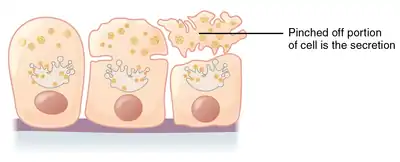

Apocrine (/ˈæpəkrɪn/)[1] is a term used to classify the mode of secretion of exocrine glands. In apocrine secretion, secretory cells accumulate material at their apical ends, and this material then buds off from the cells, forming extracellular vesicles. The secretory cells therefore lose part of their cytoplasm in the process of secretion.

| Apocrine – by membrane budding (loss of cytoplasm) |